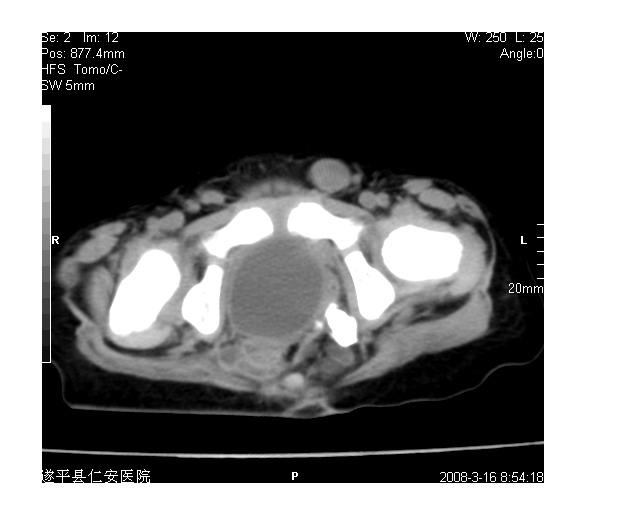

以下是引用lkc8963在2008-3-16 12:49:00的发言:[br]盆底巨大混杂密度肿块,富含多种组织成分包括脂肪/液体/软组织/钙化,边界清楚,向前压迫肠管及膀胱,向后突入骶尾部皮下脂肪层,首先考虑畸胎瘤,诊断时需要与脊柱裂/囊性淋巴管瘤等区别。